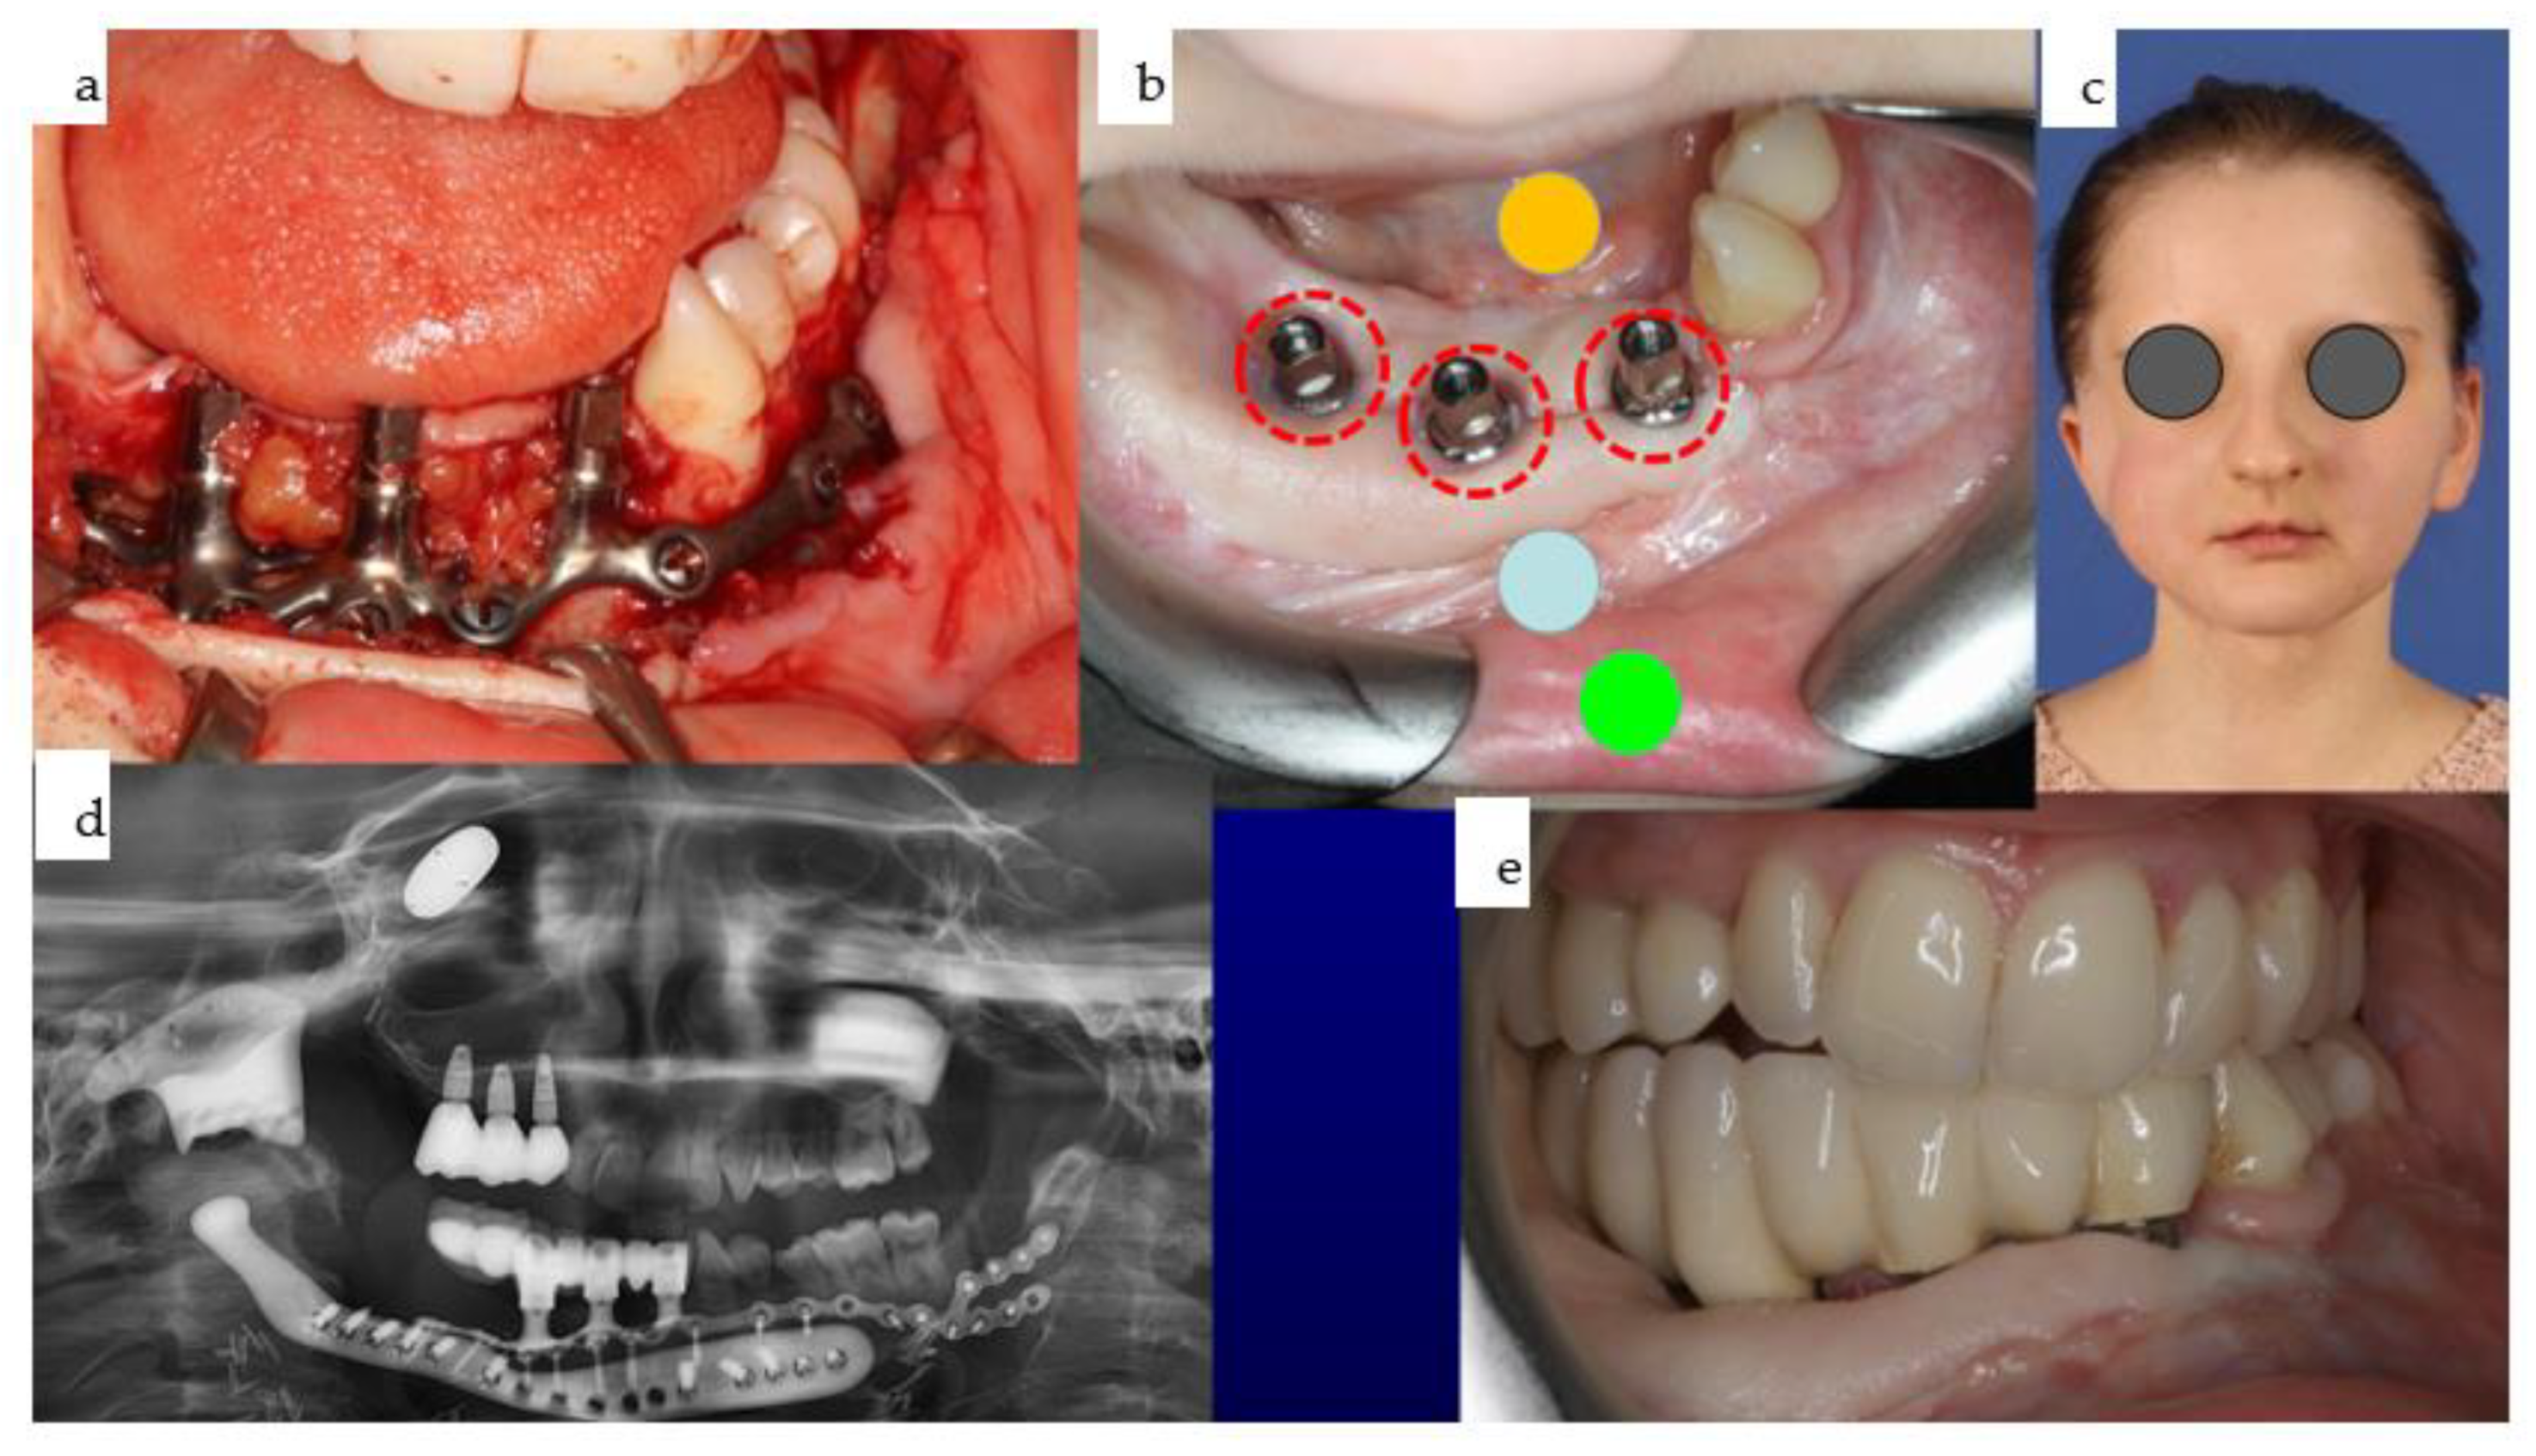

Figure 30. (ae): Different views of the IPS Implants® Preprosthetic during (a) and three months after (b) insertion are presented; the red dotted circles around the posts reveal healthy tissues (b). The yellow (floor of the mouth), light blue (vestibule), and green (inner lining of the lip) spots demonstrate the successful subunit separation due to the additional microvascular radial forearm flap, which was placed ahead of bimaxillary dental rehabilitation. The clinical appearance is depicted in (c); the orthopantomogram summarizes all biomaterials and implants placed into the patient over many years, including the gold weight implant for the right upper eyelid, patient-specific PEEK implant (non-radio-opaque) for the right temporal fossa (only fixation screws are visible), right total joint replacement, IPS Implants® Preprosthetic with mounted final superstructure, and the conventional three bone-level tapered dental implants with crowns in the right maxilla (d). An intraoral view matching the clinical picture (c) is shown in (e) with the dental arches in occlusion. Mild right mandibular sagging led to occlusal correction over time.

Soft tissue transplantation with a microvascular radial forearm flap was performed to separate the right cheek from the floor of the mouth. Three months later, a CAD/CAM-manufactured IPS Implants® Preprosthetic for the right lower jaw was combined with guided-surgery insertion for three conventional dental implants in the right maxilla (Figure 29 and Figure 30). Finite Element Method (FEM) analysis guided the design of the subperiosteal implant, limiting the metallic footplate around the post-carrying suprastructure and incorporating an extension as a boom to the contralateral mandible, ensuring a safe distance from the natural dentition and the patient-specific mandibular implant above the left mental nerve.

2.4.6. Surgical Procedure

During an outpatient procedure under general anesthesia, the subperiosteal implant was securely fixed with 18 2.0 screws, varying in length from 7–13 mm. A screw-retained provisional prosthesis with a high-water design was mounted to prevent compression of the underlying soft tissue (Figure 30). The drill guide for the guided surgery protocol was designed using coDiagnostiX® software and printed in-house with autoclavable resin. Generic sleeves, narrowed to a 5 mm inner diameter with resin, were used instead of metallic sleeves. This modification, which was validated in our in-house dental lab, was employed alongside conventional Straumann reduction spoons during the ascending drilling protocol for dental implant placement. The final prosthesis was screw-retained due to inadequate interocclusal space for a removable denture (Figure 31).

2.4.7. Adjustments and Outcome